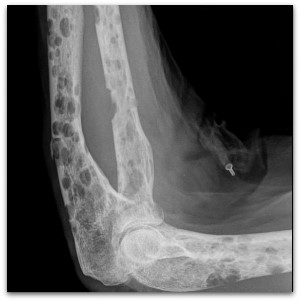

В пределах миеломы ткань кости будет постоянно рассасываться, в губчатой кости будут пропадать перекладины и истончаться кортикальный слой. Он может полностью разрушиться, в этом случае опухоль прорастет под надкостницу, поднимет ее и будет продолжать расти на кости.

Делают рентген, проводят анализы крови и мочи, также можно делать МРТ при множественной форме.